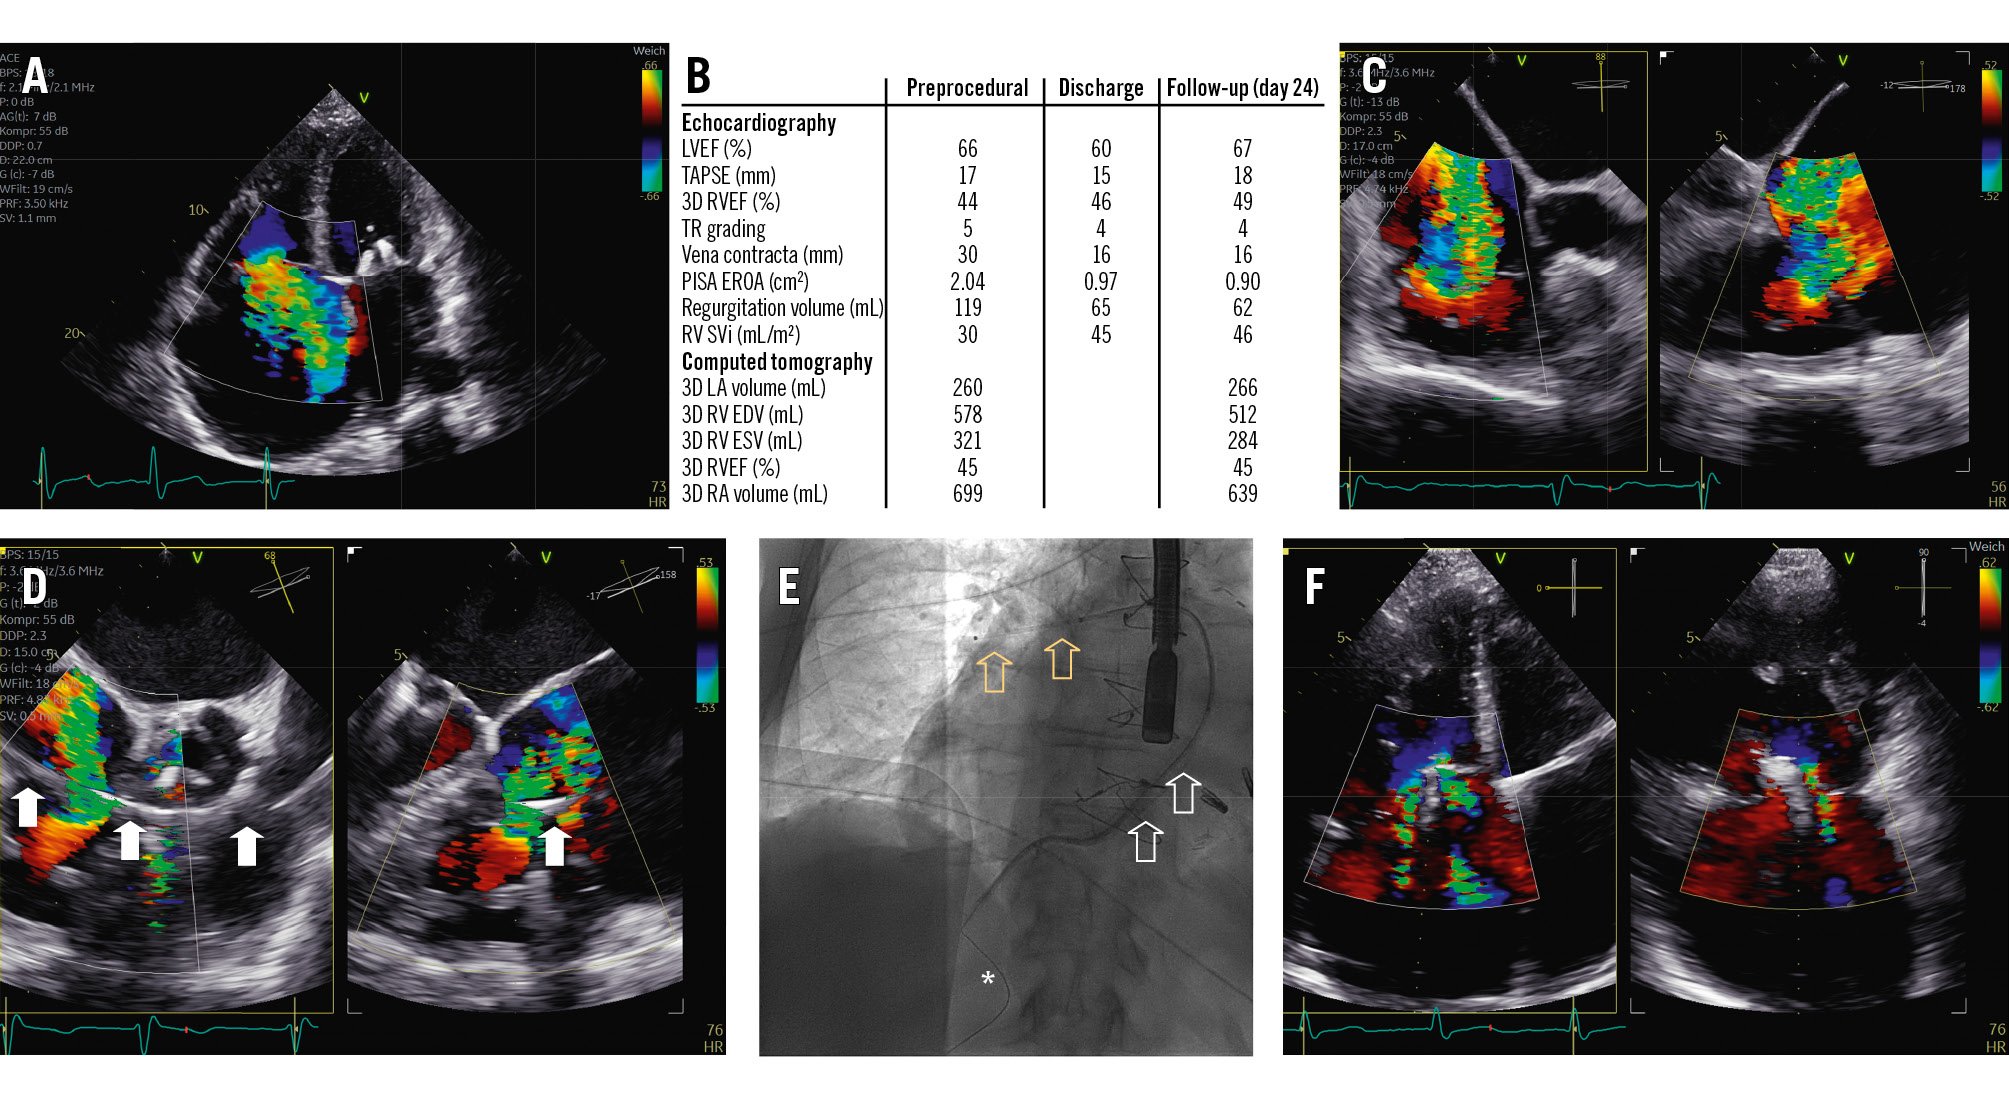

An 81-year-old male with torrential functional tricuspid regurgitation (TR; biplane vena contracta [VC] width 30 mm, effective regurgitant orifice area [EROA] 2.04 cm²) (Figure 1A-Figure 1B-Figure 1C, Moving image 1-Moving image 2-Moving image 3) suffered from recurrent episodes of congestive heart failure despite optimal medical therapy, including an extensive diuretic regimen. Given the advanced stage of his disease, with severe dilatation of the tricuspid annulus (diameter 72 mm, gap 18 mm) and inferior vena cava (IVC; diameter 65 mm), none of the currently available devices were deemed suitable. Other echocardiographic findings showed preserved left and borderline right ventricular (RV) function (three-dimensional [3D] right ventricular ejection fraction 44%, tricuspid annular plane systolic excursion 17 mm, fractional area change 33%), yet an impaired RV stroke volume index (SVi; 30 mL/m²) (Figure 1B). Right-heart catheterisation excluded any form of pulmonary hypertension. Medical history included permanent atrial fibrillation and previously conducted coronary artery bypass graft surgery, as well as mitral transcatheter edge-to-edge repair. Since screening for all commercially available devices (including transcatheter annuloplasty, transcatheter edge-to-edge repair and transcatheter valve replacement) remained unsuccessful, application for off-label utilisation (compassionate use) of a novel transcutaneously implanted spacer (Pivot Extend [Tau Medical]) was permitted by national authorities.

The procedure was conducted under general anaesthesia with transoesophageal echocardiographic guidance. As the first step, a stiff wire was placed in the right lower pulmonary artery branch by successive exchanges via right femoral vein access. Subsequently, the position of the wire was assessed in the right ventricle to exclude entanglement and/or interference with the tricuspid subvalvular apparatus and papillary muscles (Moving image 4, Moving image 5). The device was then brought into position (Moving image 6), and its body was inflated to a diameter of 12 mm, which resulted in approximately 50% reduction of TR (Figure 1B, Figure 1D, Figure 1E). Finally, the spiral anchor was deployed into the IVC without any notable complications. Besides macrohaematuria due to urinary catheter placement, postprocedural observation remained uneventful. Discharge echocardiography showed massive TR (VC width 16 mm, EROA 0.90 cm²) with an improved RV SVi of 45 mL/m², which was also confirmed at ambulatory follow-up (Figure 1B, Figure 1F, Moving image 7, Moving image 8).

Figure 1. Overview of periprocedural imaging and procedural results. A) Torrential TR severity. B) Measurements by transthoracic echocardiography and computed tomography at baseline, discharge and follow-up. C) Intraprocedural transoesophageal echocardiography confirming TR severity. D) The spacer (arrows) already in position with reduction of TR by approximately 50%. E) Final positioning of the device (white arrows) with its respective spiral anchor (asterisk) and elephant trunk (yellow arrows). F) Residual TR at follow-up. 3D: three-dimensional; EDV: end-diastolic volume; ESV: end-systolic volume; EROA: effective regurgitant orifice area; LA: left atrial; LVEF: left ventricular ejection fraction; PISA: proximal isovelocity surface area; RA: right atrial; RV: right ventricular; RVEF: right ventricular ejection fraction; SVi: stroke volume index; TAPSE: tricuspid annular plane systolic excursion; TR: tricuspid regurgitation